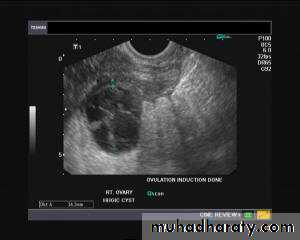

Hemorrhagic ovarian cysts:

Hemorrhagic cyst of ovary resulting from Ovulation induction

This young nulliparous female patient undwerwent ultrasonography following ovulation induction. The right ovary shows a typical hemorrhagic cyst formed from the corpus luteum. The first image (top row- left) is a transabdominal ultrasound image showing fine fibrinous strands within the cystic mass in the right ovary. Transvaginal ultrasound and color Doppler images confirm these findings. The uterus shows typical secretory changes in the endometrium suggesting post ovulatory phase.